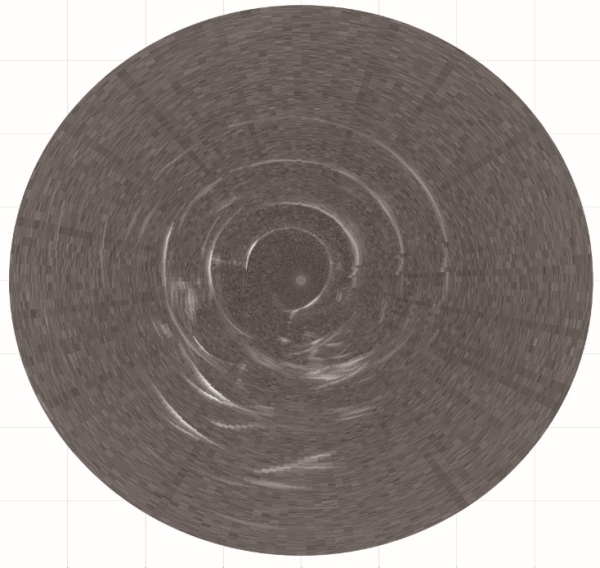

圖2.多頻超聲內窺鏡所獲得的多層仿體超聲圖像